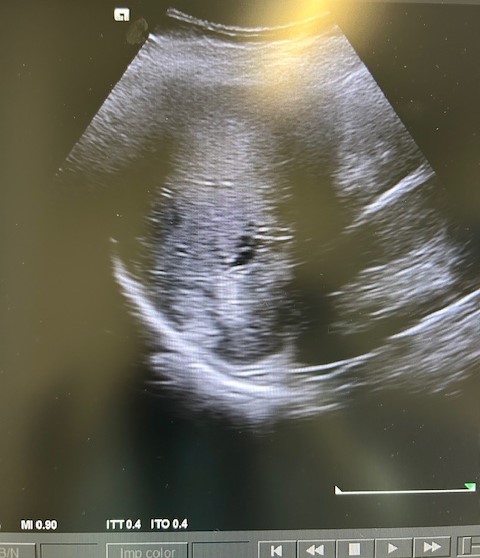

Descripción de los hallazgos ecográficos y las imágenes más relevantes para la resolución del caso

En la ecografía podemos apreciar hepatomegalia > 16 cm con múltiples imágenes en su interior hiperecogénicas sugestivas de LOE. No otros hallazgos a destacar.

El paciente fue valorado en Consultas Externas confirmando el diagnóstico. Se realiza ecografía abdominal con hallazgos de múltiples nódulos hepáticos de entre 12-35mm. En la colonoscopia, neoplasia circunferencial con aumento de consistencia, áreas ulceradas y necrosis, con estenosis incompleta, siendo compatible con adenocarcinoma de sigma.